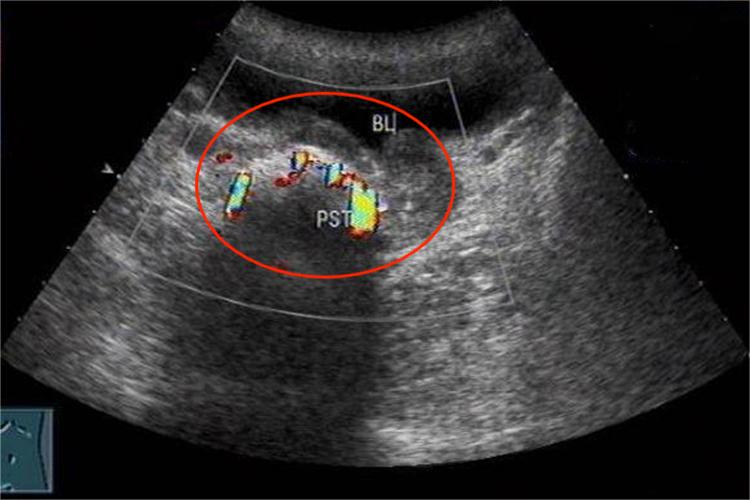

大多数单发、小的前列腺结石无临床症状,多在体检时发现。其症状亦无临床特异性,可表现为慢性前列腺炎的症状,如会阴部疼痛、腹股沟区及肛周不适、隐痛及阴茎部疼痛,有些患者可出现性功能障碍。部分患者可有结石排出。感染严重形成前列腺脓肿者,可出现全身性症状如发热等,局部症状明显,会出现会阴疼痛剧烈,大便时加重。患者进行B超检查可发现前列腺腺体内强回声,数目不一,大小可从点状至1cm,数目多、成簇状的前列腺结石多位于内外腺交界处,结石可伴有或不伴有声影。